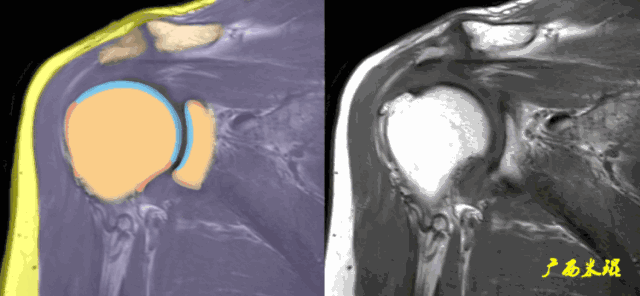

1、斜冠状位:平行于冈上肌腱长轴,主要评估冈上肌。